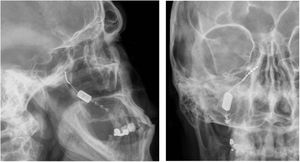

Neuromodulation of the ipsilateral sphenopalatine ganglionInitial experience with the use of non-implanted electrodes to stimulate the sphenopalatine ganglion (SPG) ipsilateral to CH pain shows that the treatment is effective in 61% of patients.17,67 A microstimulator has since been designed that can be implanted in the SPG following CT imaging analysis of the pterygopalatine fossa68 and antibiotic prophylaxis. The device is placed transorally with a minimally invasive gingival approach, with the patient under general anaesthesia and admitted to hospital for 24 hours.69 Intraoperative navigation techniques may be used, and a simple radiography is used to verify the position of the stimulator (Fig. 4).70

Profile and anteroposterior radiography images showing a wireless neurostimulation device implanted in the pterygopalatine fossa of a patient with chronic refractory cluster headache in the ipsilateral side. Image courtesy of Dr José Miguel Láinez of Hospital Clínico Universitario de Valencia (Spain).

The stimulator is powered and activated by a wireless remote controller held to the patient’s cheek; therefore, it does not require leads or a subcutaneous generator, and surgical procedures to change batteries are not necessary.